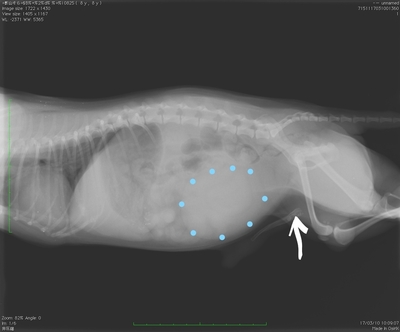

犬 膀胱結石. 犬の尿石症 コーギーの1例 手術で膀胱結石を摘出しました 尿石症とは? 尿石症(尿路結石)とは、尿路である腎臓(腎盂)、尿管、膀胱または尿道のいずれかに結石が形成される病気です。 猫の特発性膀胱炎(FIC) 猫のおしっこに関する病気を総称して猫下部尿路疾患(FLUTD)と呼びます。 その症状として、血尿、頻尿、排尿時に痛がる、ト 排尿障害 〝何度. 膀胱と腎臓を繋ぐ管に出来る尿管結石 3膀胱に出来る膀胱結石 4尿道に石が詰まる尿道結石 犬の結石には4種類あり原因となる野菜・食べ物は異なる. 犬の膀胱・尿道結石の一例 小手指ペットクリニック 16年11月28日 8才のワンちゃんが、昨日から尿が出ずに元気がないとのことで来院されました。 レントゲンを撮ると、膀胱内に7個程度、尿道に3個(ペニス先端から10cmに2個、13cmに1個)の石が.

犬 膀胱結石・尿道結石 チワワ 10歳11ヶ月齢 去勢オス 71kg 頻尿と血尿、排尿障害を主訴に来院 腹部と陰茎の触診検査にて結石症が疑われたため、 レントゲン検査を行い、膀胱結石および尿道結石、腎臓結石と診断した 尿道内にぎっしりとつまった結石は、カテーテルにて膀胱内に押し戻し、膀胱切開にて膀胱結石を摘出した 腎臓結石はに対する外科処置は、腎臓. 犬の膀胱結石 更新日時: ミニチュアダックスフンド、オス (去勢)、11歳 《主訴》血尿、排尿しづらい (少量ずつしか出ない) 《検査》①腹部レントゲン検査 膀胱に結石と思われる不透過性陰影を多数確認 ②腹部超音波検査 膀胱内に結石と思われるシャドーを引く高エコー物を多数確認 ③尿.